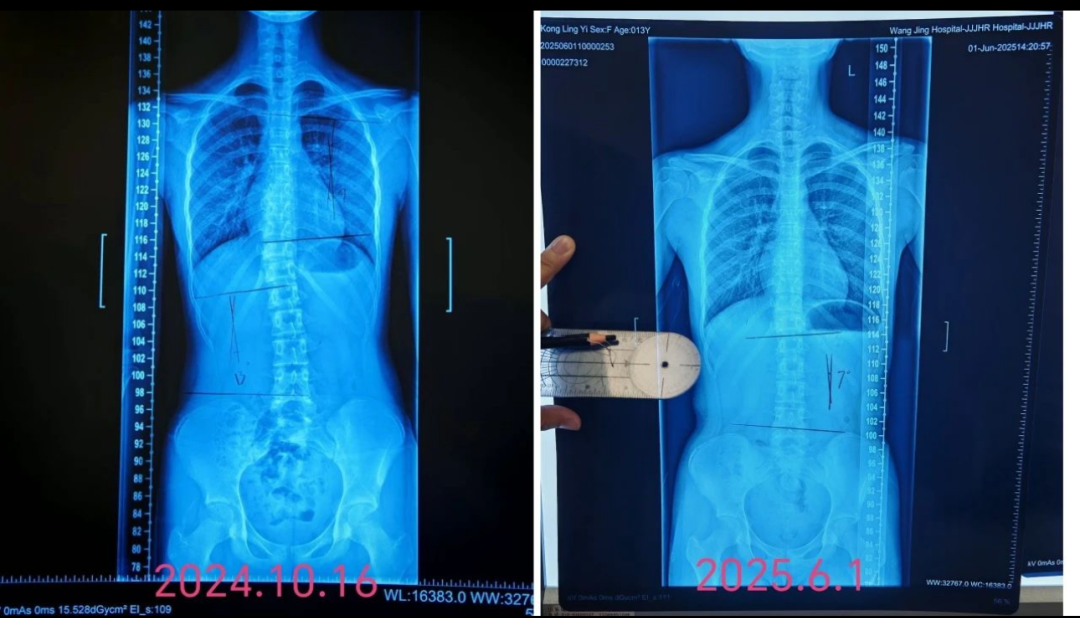

据中心负责人史清钊老师介绍,目前康复训练中心运营情况良好,服务范围涵盖了运动损伤康复、慢性疾病康复、脊柱侧弯矫正、术后康复等多个领域,为运动员、普通市民以及各类需要康复服务的人群提供了个性化的康复方案。通过精准的评估、科学的训练和专业的指导,帮助患者恢复身体功能,提高生活质量。